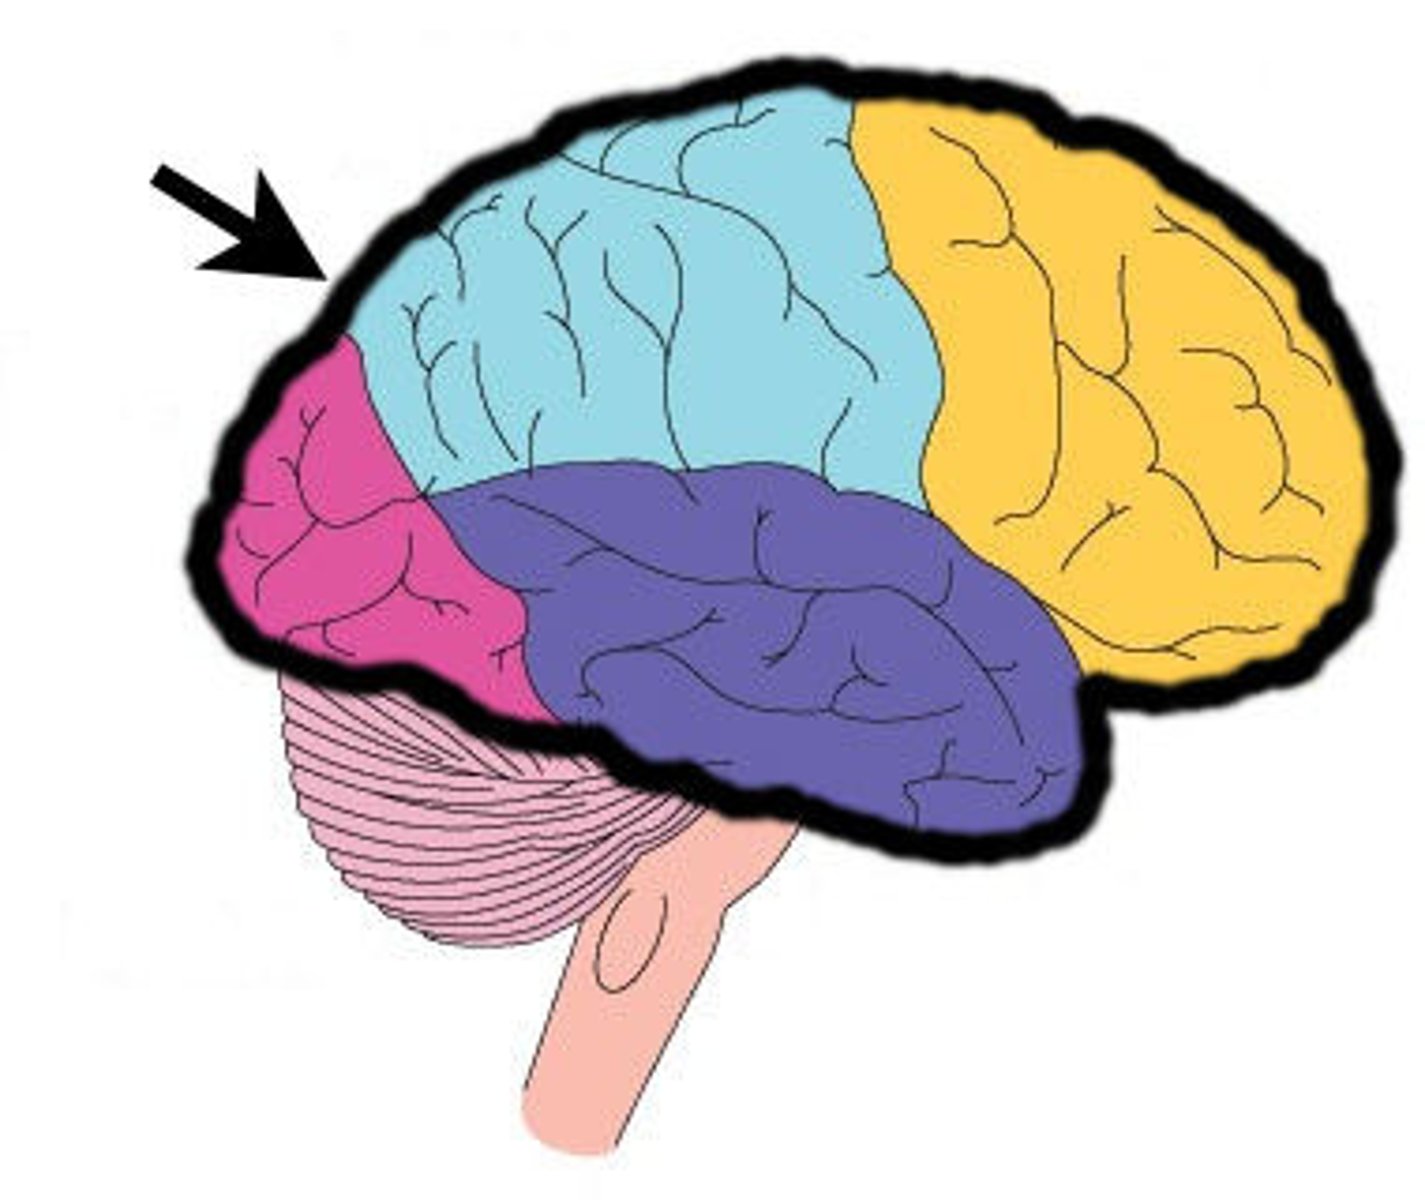

frontal lobe

temporal lobe

parietal lobe

occipital lobe